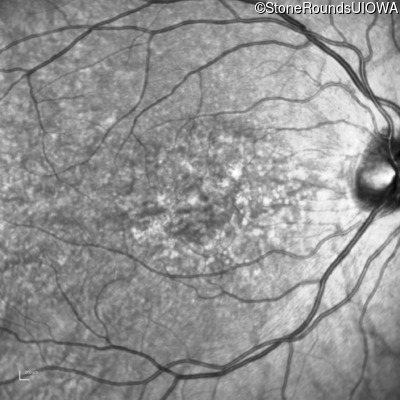

Infrared Fundus Photograph - Right - 20/15 -1 sc

Exemplar